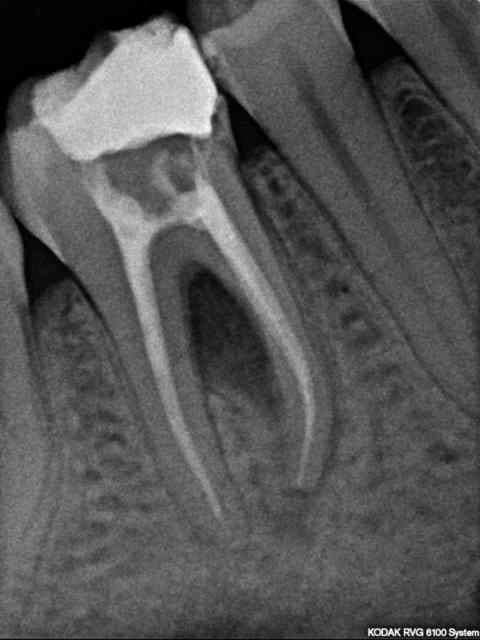

Patient de 22 ans, RAS au niveau général, bonne hygiène.

46 nécrosée avec image de perte osseuse inter-radiculaire. Pas de mobilité, pas d'épisode infectieux aigü.

Que lui proposeriez-vous en 1ère intention ? Uniquement le traitement radiculaire et surveillance de la cicatrisation ou bien d'emblée une chir avec ROG ?

La sémiologie radio indique une lésion combinée endo-paro à point de départ endodontique.

A mon avis, selon un schéma étiologique classique

1-traiter l'etiologie : traitement endodontique

2-réévaluation a 8 semaines de la furcation : pas d'amélioration -> chir paro.

Bien qu'il manque quelques données cliniques : sondage ? modification gingivale ? Pour moi, c'est une lésion purement d'origine endodontique.

Il n'y a aucune perte osseuse inter-dentaire. L'atteinte est inter-radiculaire pure sans communication avec la cavité buccale (si absence de fistule parodontale) et le traitement endodontique, réalisé sous digue bien entendu, suivi d'une restauration coronaire étanche est la solution thérapeutique.

Surtout, il faut éviter toute intervention chirurgicale précipitée, tu as encore, même si elle n'est visible à la radiographie, toute la trame collagénique encore en place. Le potentiel de cicatrisation de ce type de lésion est optimal.

Traitement comme Céramik: endo + reconstruction coronaire et attendre.